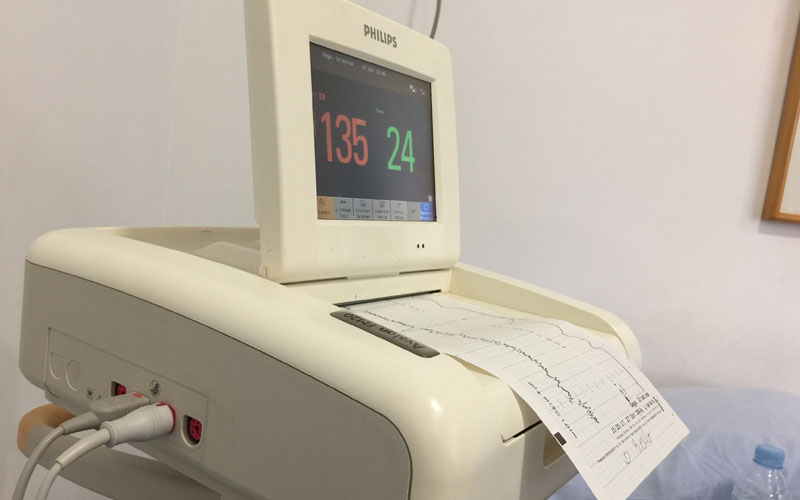

Monitores y revisión

Volviendo al Hospital… llegamos y me pusieron en monitores, las contracciones seguían igual y estaba dilatada de 1 centímetro. Después de un buen rato allí, el Doctor que había de urgencias decidió enviarnos a casa diciéndonos que podía ponerme de parto esa misma noche, como podía tardar algunos días más. Que volviera cuando las contracciones fueran cada 5 minutos o rompiera aguas. No me hizo ninguna ecografía, algo que en ese momento pasamos por alto, o dimos por hecho que sabía lo que hacía. Al fin y al cabo, él era el médico y nosotros un manojo de nervios. Después nos daríamos cuenta del error…

Llegó el jueves, 3 de noviembre. Me tocaba consulta normal, monitores y revisión para ver cómo iba la cosa. Yo ya había salido de cuentas (el 1 de noviembre) y pasé toda la semana con contracciones cada poco tiempo, pero no llegaban a los 5 minutos «de rigor». Además de la visita a urgencias del lunes y las contracciones que seguían en las mismas, todo normal, o eso creíamos.

Entré en la consulta pidiendo que me lo sacaran, había pasado toda la semana igual y sin poder dormir porque el dolor era cada vez más intenso. Le expliqué a mi Doctor (el que me había llevado el embarazo desde el principio) que creía haber expulsado el tapón mucoso. Miró la gráfica de los monitores, me hizo una ecografia, un tacto (¡ya estaba de 3 centímetros!) y dijo: «Creo que te voy a hacer caso».